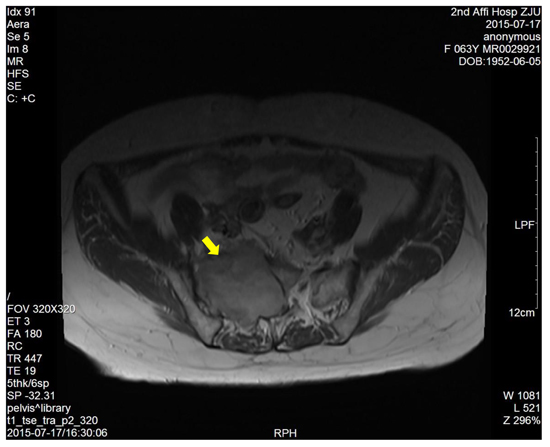

The dimension of the tumors was also shown in Table 1. Lumbosacral CT of our cases were characterized by expansive lesions located in high-sacra such as sacrum 1 and 2, mass appearance on the lateral caudal, well-circumscribed lesions with marginal sclerosis, and the overall benign presentation (Figure 1). In our study, the typical findings of sacral schwannomas in MRI were a well-circumscribed lesion with a heterogenous signal intensity on T2-weighted image. On T2-weighted image, low signal intensity was mixed on the basis of high signal intensity, which was found in our all cases (Figure 2). On T1-weighted image, slightly high signal intensity was mixed on the basis of low signal intensity, which was shown in two cases (Figure 3). Low signal on T1-weighted image was shown in eight patients (Figure 4). T1-weighted images of all cases are characterized by heterogenous enhancement (Figure 5). Average blood loss during surgery was 980ml (ranging between 100 and 2,000ml). Seven patients had only posterior approach as their tumors were limited to the sacrum; two patients went through both anterior and posterior interventions as their tumors extended to the anterior and posterior bone limits of the sacrum; one had just anterior intervention because the tumor was localized to the presacral region. All patients underwent an intralesional resection (piecemeal subtotal excision or shaving) to identify and preserve sacral nerve roots as much as possible. All patients were performed histological examinations after surgery to confirm the diagnosis of sacral schwannomas. Two patients had postoperative bowel and bladder dysfunction after surgery. But they gradually recovered after four months and three weeks, respectively. One patient had cerebrospinal fluid leakage and secondary intracranial infection. This patient finally recovered after several lumbar drainage and anti-infection treatment. All patients were ambulatory postoperatively.

Figure 5: The enhanced T1-weighted image showed a right sacral mass with uneven enhancement.